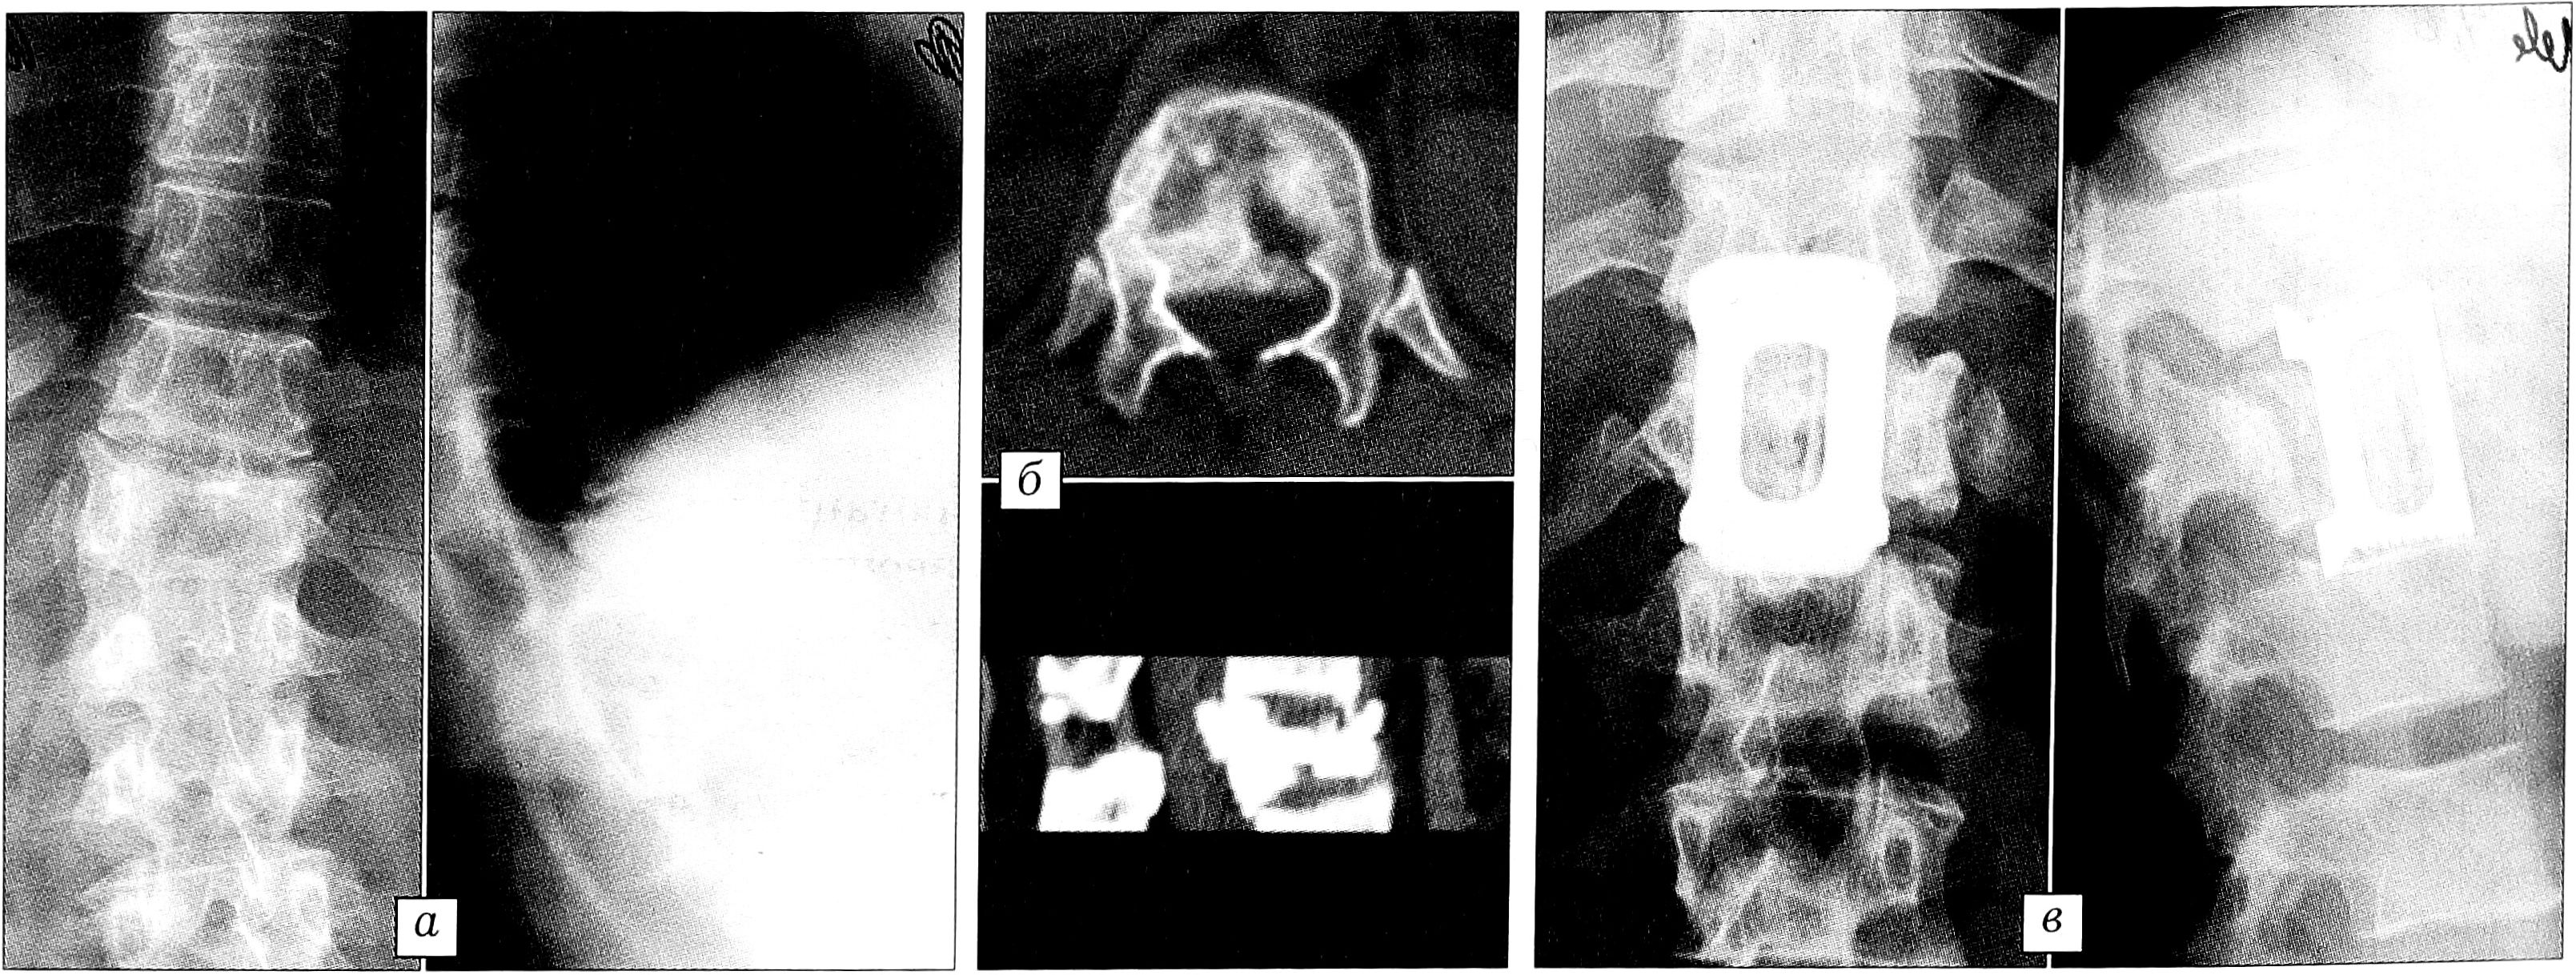

При оскольчатых вертикальных переломах тела позвонка без значительного разрушения и дислокации краниальной и каудальной замыкательных пластинок, флексионно-дистракционных горизонтальных переломах, проникающих переломах на фоне выраженного остеопороза достаточен корригирующий транспедикулярный остеосинтез, в случае выраженного остеопороза — дополненный спонгиозопластикой. При нестабильных взрывных переломах с выраженной дислокацией дорсального фрагмента в позвоночный канал, когда разрушены вентральная и средняя колонны — тип В (рис. 3), при ротационно-экстензионных переломовывихах позвонков — тип С (рис. 4) требуются выполняемые одномоментно или последовательно дорсальный корригирующий остеосинтез и вентральный спондилодез, при необходимости в сочетании с передней декомпрессией.

Рис. 4. Больной В. 24 лет. а — рентгенограммы до операции: переломовывих Т12 позвонка, кифосколиоз; б — компьютерная томограмма до операции; в — рентгенограммы после задней мобилизации, устранения вывиха, коррекции кифоза, бисегментарного спондилодеза, аутопластики, транспедикулярной фиксации Т11-L1 позвонков.